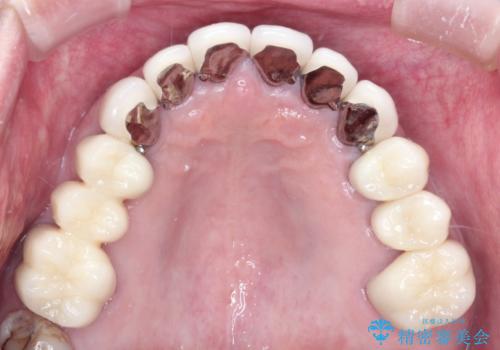

奥歯が欠損しており、上下の前歯が強く咬合する可能性があったので、上顎前歯の裏側は金属のものにしました。

上顎は全体的にクラウンの入れ替えと、下顎はインプラントの提案もしましたが、希望されなかったのでノンクラスプデンチャーの製作をする治療計画としました。